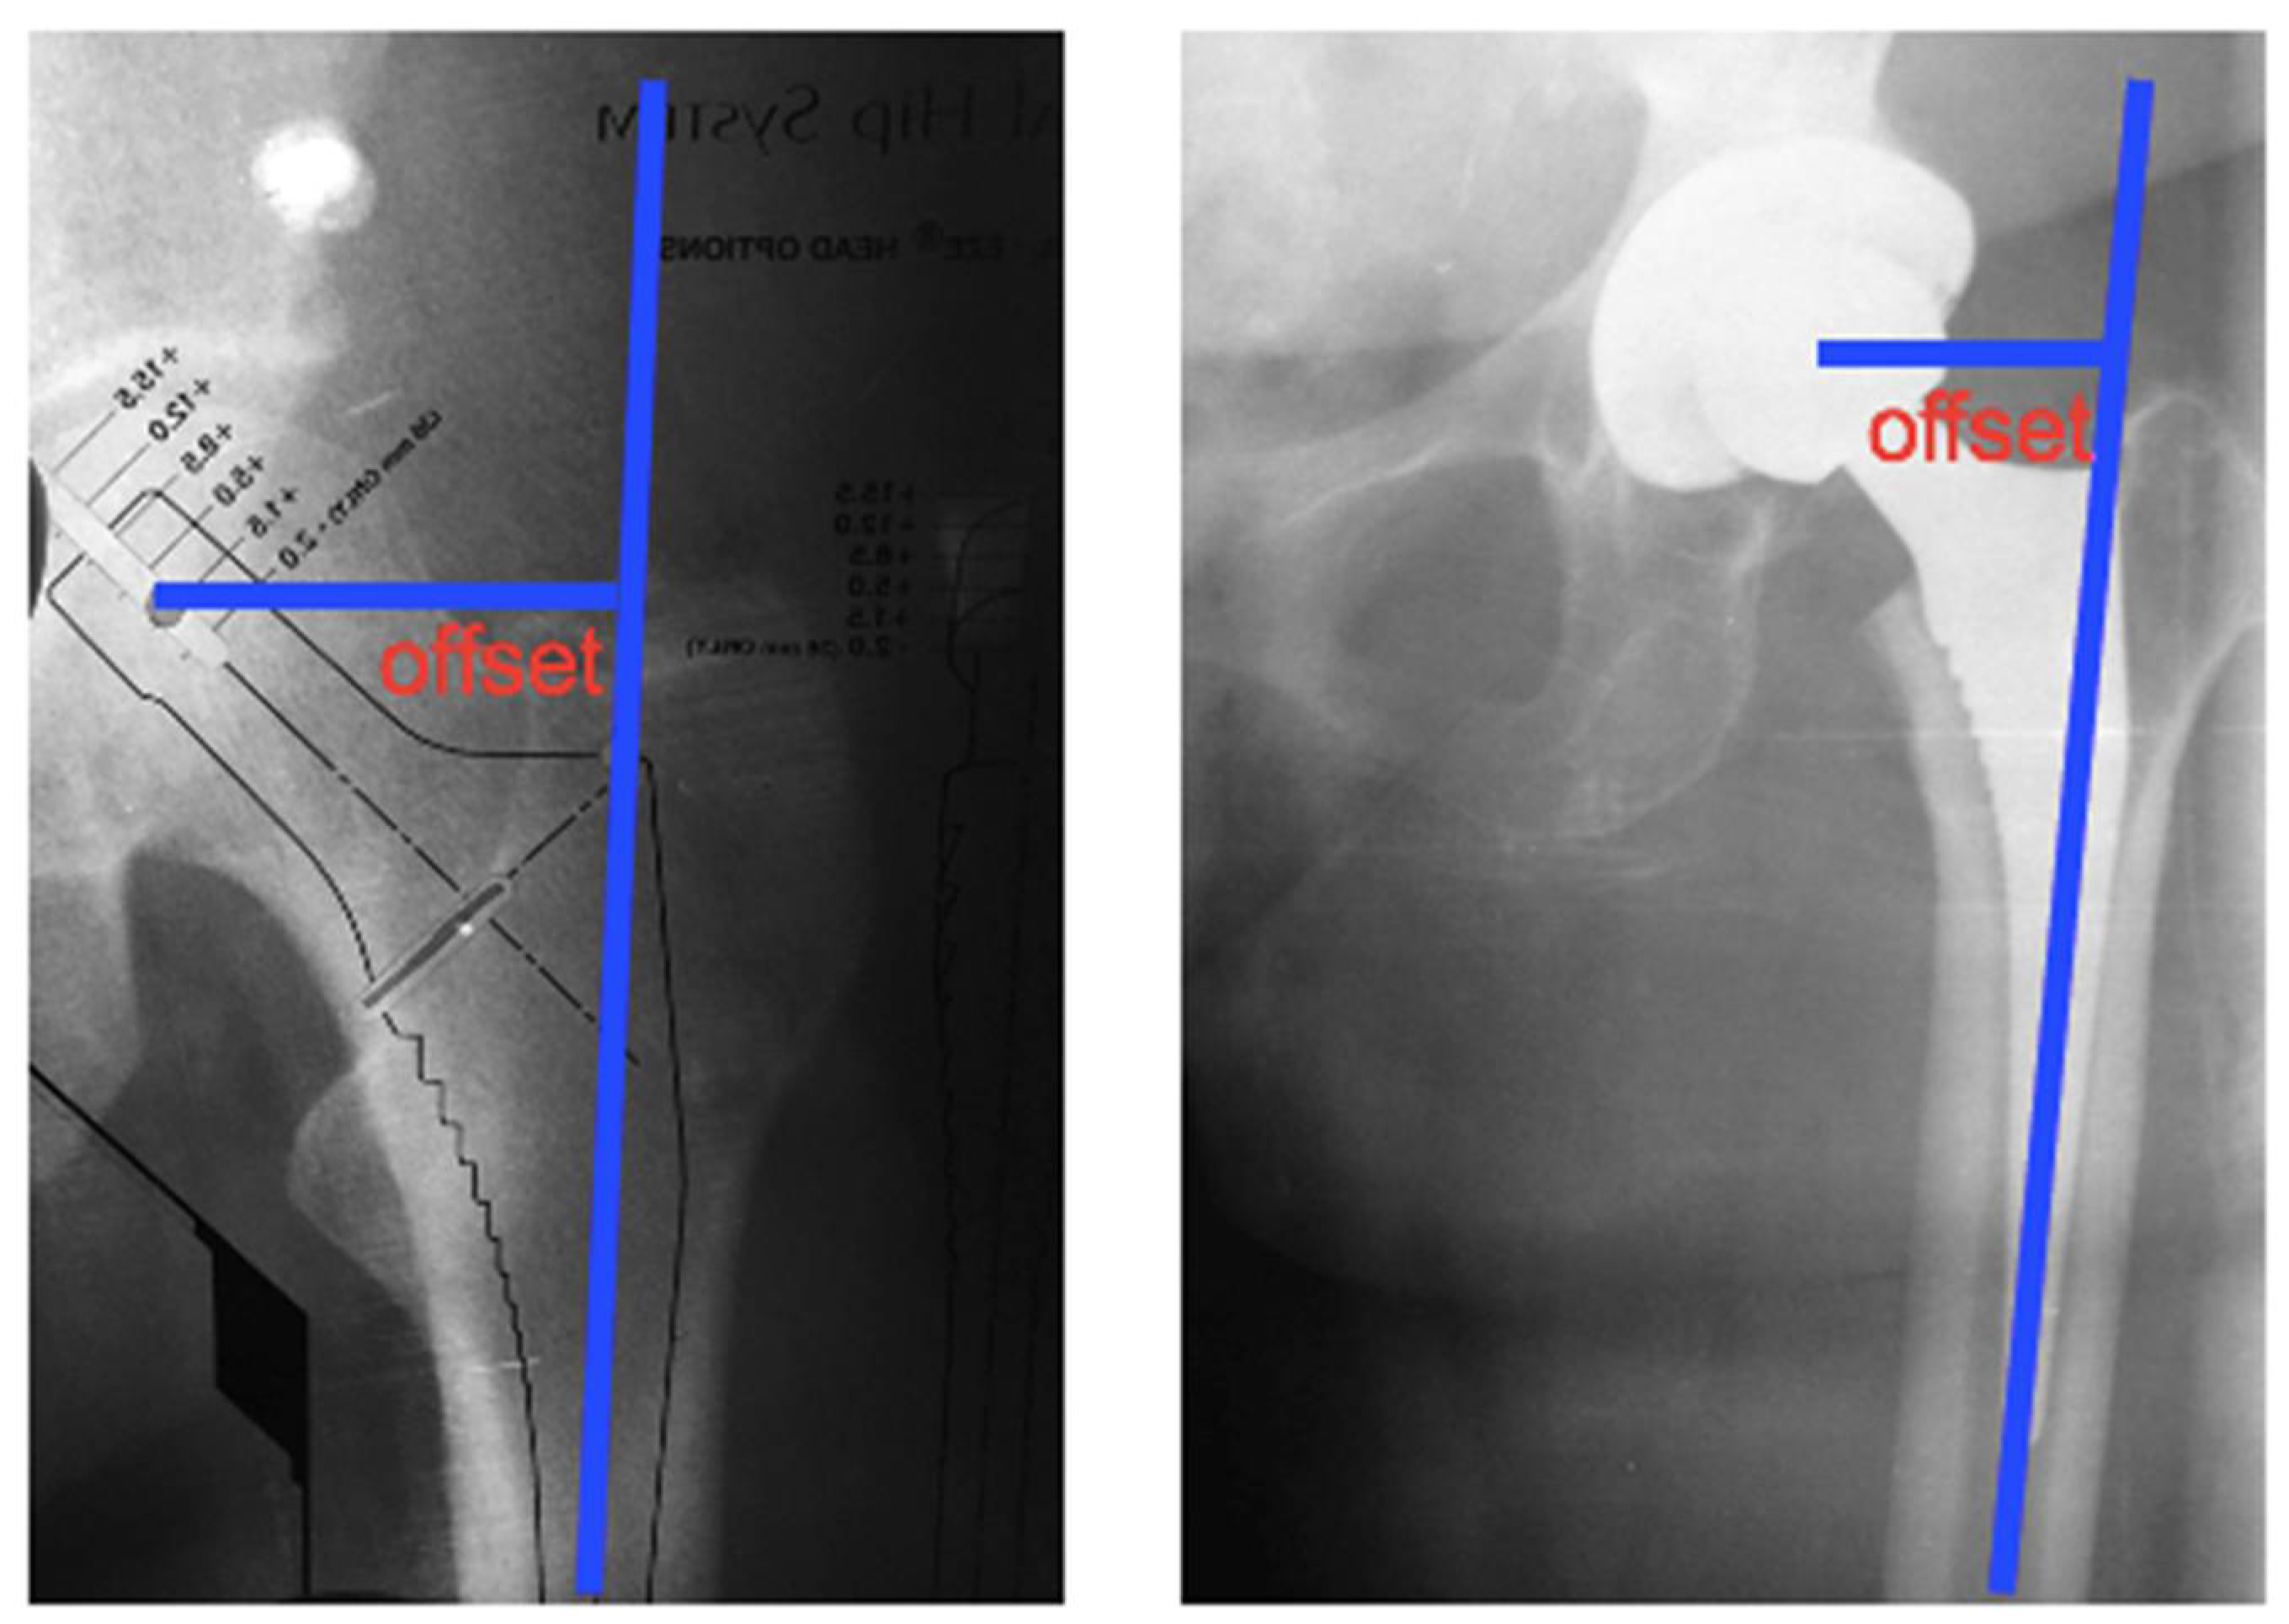

2.3. Analysis of Radiographic Parameters: Positioning and Inclinations of the Acetabular Component

| Implant Femoral Offset (cm) | 4.5 ± 0.7 | 4.5 ± 0.6 | 0.102 |